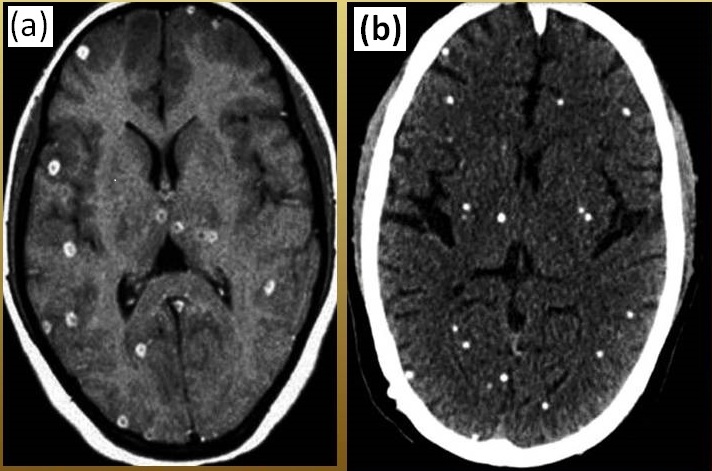

All the patients (N=50), who participated in the present study, were enrolled in the OPD of the department of neurology, IMS, BHU. Figure-1 represented the entire overview of the diagnosis of patients with NCC. All the diagnostically confirmed cases (MRI /CT scan based imaging) of NCC were included in the present study (Figure-2).

Figure 2: Representation of the diagnostic confirmation of (a) MRI of nodular cysticerci (multiple)

, (b) CT scan of calcified cysticerci (multiple)